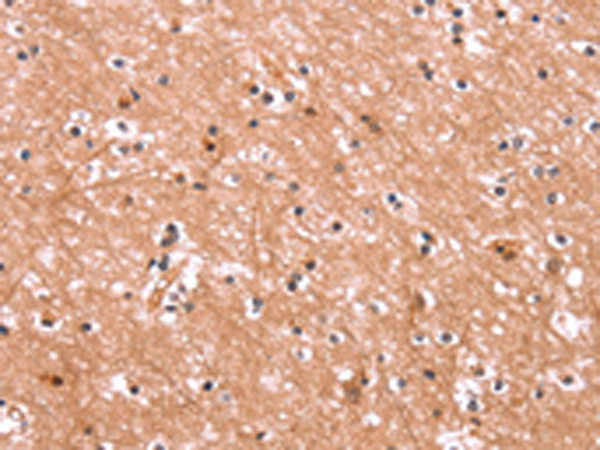

IHC positive control: |

Human brain and Human liver cancer |

IHC Recommend dilution: |

25-100 |